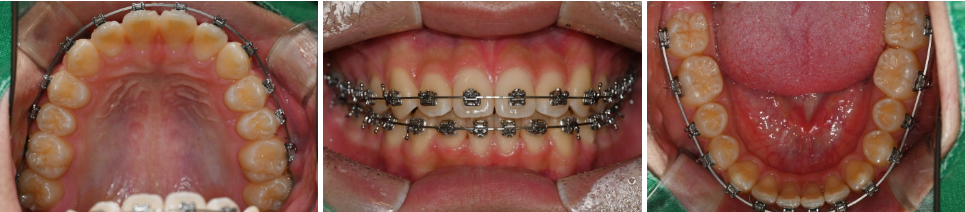

24.05.02

24.10.11

거의 모든 공간이 폐쇄되었을 때

전체적인 얼굴 모습을 확인하며

발치 여부를 판단한 결과,

24.07.05

비발치교정으로 마무리하는 것으로

결론을 내렸습니다.

25.01.14

다음은 교정 후 모습입니다.

앞니 사이 벌어짐 과 뻐드러짐 이

단번에 개선되면서 치아각도도

올바르게 세워졌습니다.

앞니가 가지런하게

안쪽으로 모이면서 안모에도

좋은 변화가 찾아왔습니다.^^